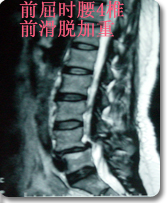

后路内窥镜下(XTube)经单侧神经孔腰椎体间融合,椎弓根螺钉复位内固定术(TLIF)

采用后路内窥镜下(XTube)经单侧神经孔腰椎体间融合,椎弓根螺钉复位内固定术,以治疗极外侧腰椎间盘突出(神经孔型)伴腰椎不稳。 优点:通过单侧经神经孔入路途径达到椎间隙,从而达到椎间减压和植骨融合目的。该手术途径单侧入路,显露清楚,不需过度牵拉神经。为外科医生提供了一个能显著减少PLIF手术的很多风险和限制的融合方式。本手术将内窥镜(XTube)与TILIF手术的优点集于一身达到更小的创伤更好的手术效果。